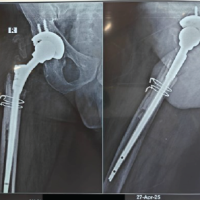

Stage 1 surgery was done via a posterior approach through the previous scar. Intraoperatively, after opening the fascia lata, we noticed a large soft tissue mass around the trochanter and acetabular region which was dark reddish brown in color. There was severe osteolysis around the acetabulum and trochanteric region. After the excision of the soft tissue mass, the material was sent for histopathology and culture (Fig. 5b). The acetabular component was completely loose, so it was removed along with the ceramic liner (Fig. 5a). There was no damage seen on the ceramic femoral head and acetabular liner. The trunnion of the femoral stem was normal. Since the femoral stem was well integrated, extended trochanteric osteotomy was done to remove the femoral stem. Extended trochanteric osteotomy was closed with encircling wiring and plating (Fig. 6). His histopathology reports showed fibrin, proliferating fibroblasts, hemosiderin-laden macrophages, lymphocytes, and chronic granulation tissue findings suggestive of pseudotumor formation. There was no evidence of malignancy (Fig. 7).

His culture report shows no growth of any organism. Postoperatively, the patient developed a serous collection around the hip for which he underwent USG aspiration. Since there was no evidence of malignancy and infection, the patient was advised for the reconstruction of the acetabulum and revision of the total hip replacement; however, the patient was not willing for surgery. Hence, the patient was started on rehabilitation using heal and sole raise and crutch support. The subsequent follow-up could not be conducted as the patient was lost to follow-up. The removed implant was not sent for any further study due to a lack of facilities.